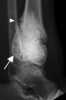

Bone grafting is a surgical procedure that replaces missing bone in order to repair bone fractures that are extremely complex, pose a significant health risk to the patient, or fail to heal properly. Some small or acute fractures can be cured without bone grafting, but the risk is greater for large fractures like compound fractures. [Source: Wikipedia ]